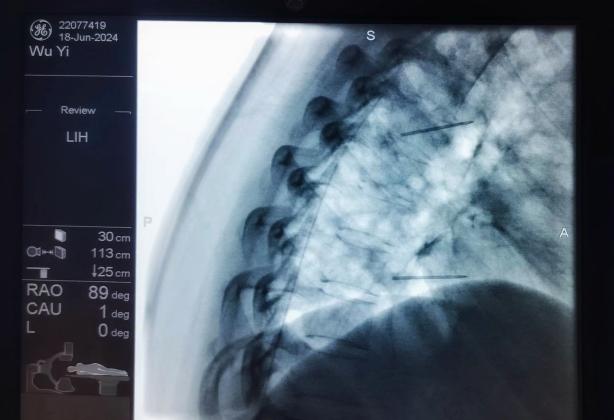

椎間盤射頻消融術、膠原酶椎間盤化學消融術